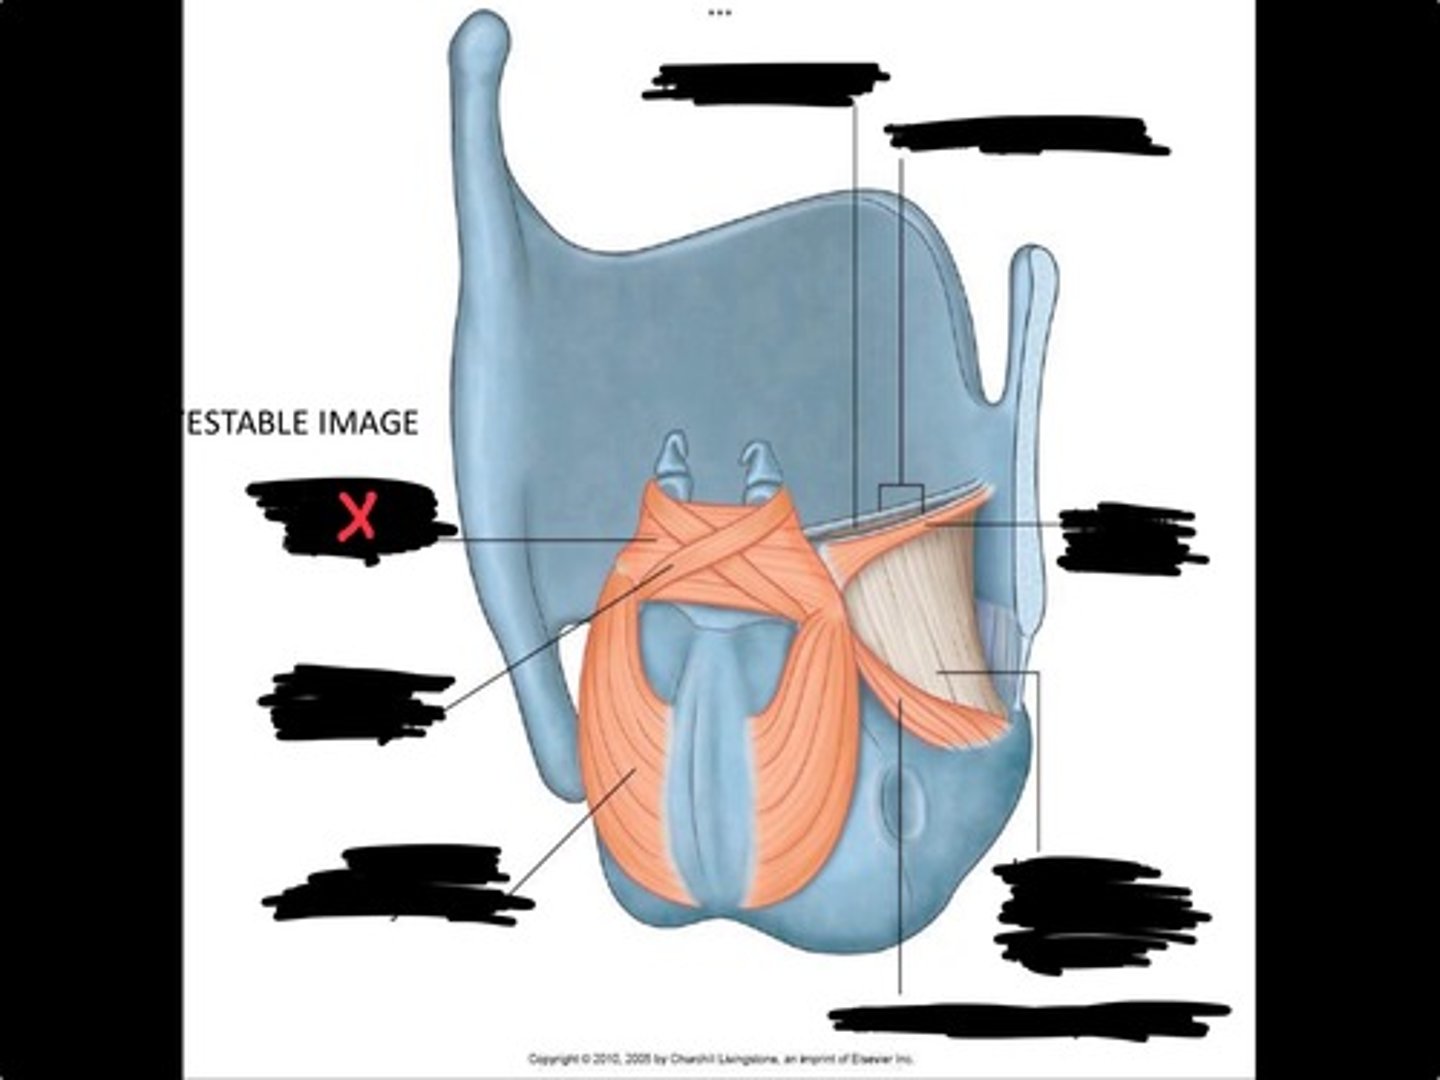

Vocal process of arytenoid

Conus elasticus

Vestibular ligament

Quadrangular membrane

Epiglottis

vocal ligament

Aryepiglottic ligament

Muscular process of arytenoid

Corniculate cartilage

Posterior crico arytenoid

oblique arytenoid

transverse artyenoid

Rima glottidis

Vocal ligament

Vocalis muscle

Lateral cricothyroid ligament

Lateral cricoartenoid